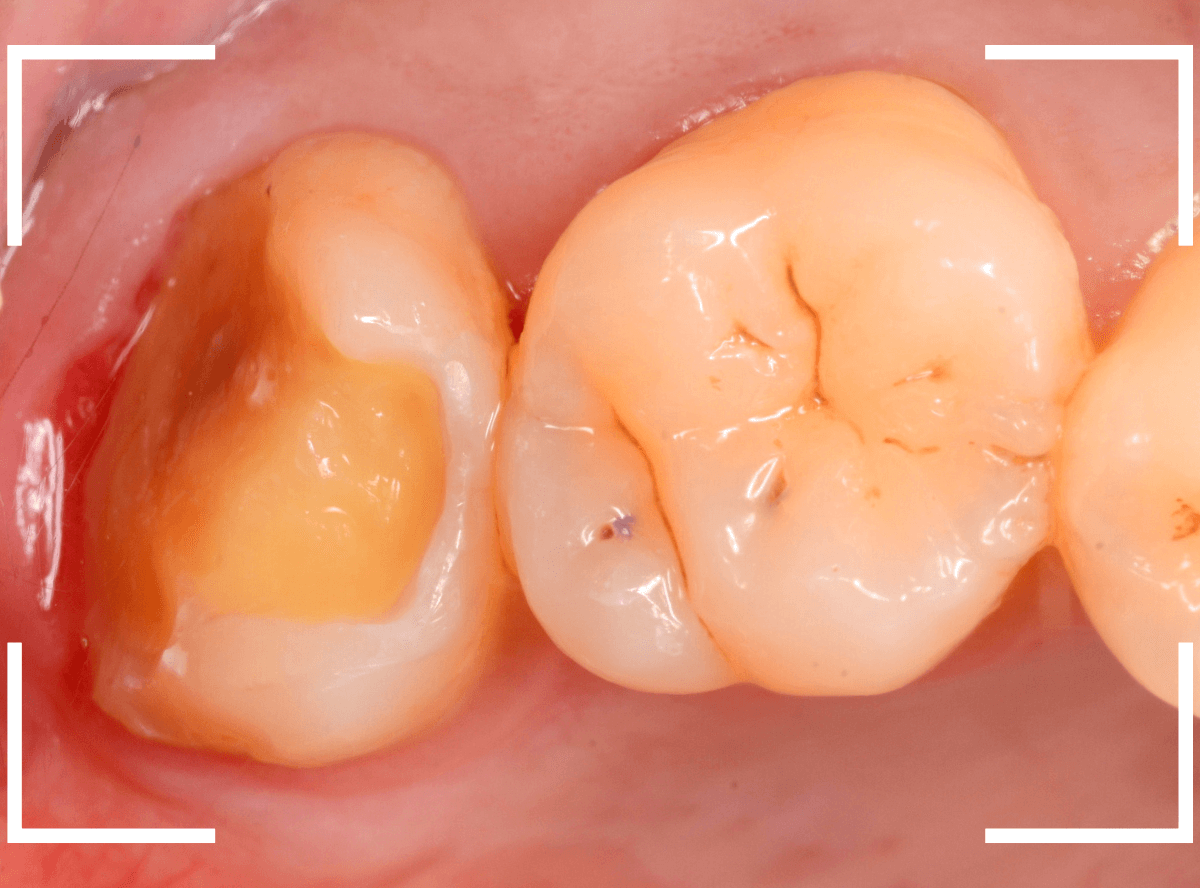

大きな虫歯でしたので、しばらく経過観察しましたが、特に症状もありませんでしたので、患者さんの希望に伴い、ジルコニア・インレーで治療をします。

セラミックが精密にsetできるように、歯をトリミングします。

模型上で精密に製作します。

治療後の状態です。

ジルコニア・インレーはE-MAX・インレーより審美性に劣るのですが、患者さんにもご満足いただける仕上がりになり、ホッとしました。